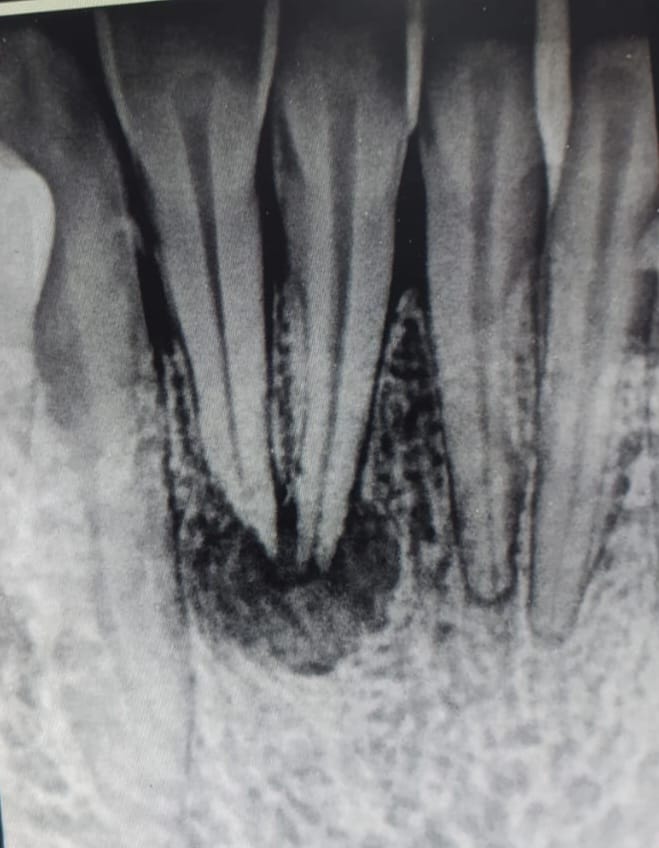

A 35-year-old male presented with the chief complaint of pain in the lower right anterior teeth. Clinical examination showed generalized discoloration due to betal nut chewing. Tooth no. 41,42 tender to percussion. Grade 1 mobility in tooth no.42

- Gum Problems: Betel nut chewing has been linked to gum problems such as gum recession, inflammation, and periodontal disease. The habit can weaken gum tissues, making them more susceptible to infections.